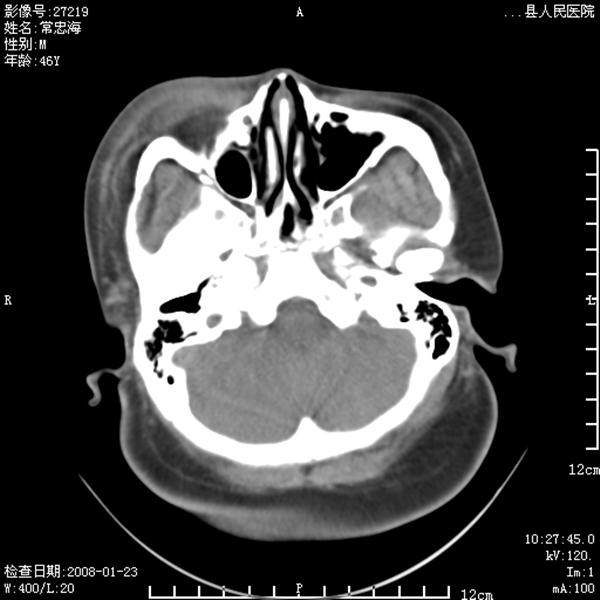

以下是引用江边学者在2008-4-19 22:26:00的发言:[br]1.胼胝体发育不良。[br]2.右侧眼球痨。[br]3.右侧颜面部软组织挫伤。